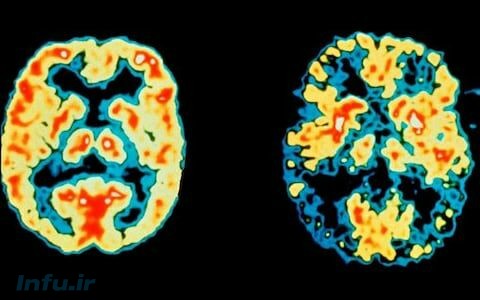

برای اولین بار، ژن آلزایمر در سلولهای مغز انسان خنثی میشود!

برای اولین بار، دانشمندان، پس از خنثی کردن مهم ترین ژن مسئول بیماری آلزایمر، مدعی کسب موفقیت در مبارزه با این بیماری شدند.

این ناشی از چندین سوء عملکرد در بیماری آلزایمر، از جمله انباشت پروتئین تاو و پپتیدهای آمیلوئید است، که (۷٫۱) درصد از بریتانیاییهای بالای ۶۵ سال را تحت تاثیر قرار میدهد.